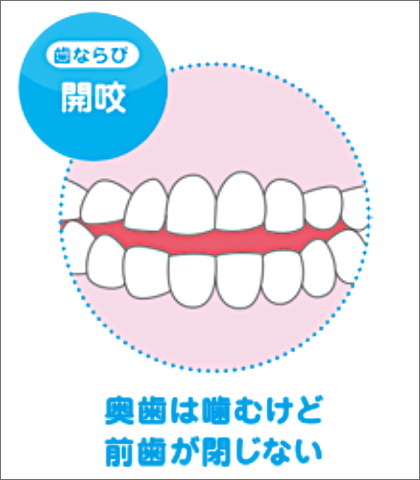

メリットは、歯ならび以外にも、噛み合わせやお口ポカン、口呼吸から鼻呼吸への改善など、お子さまを健康な体へ導くことを目的としています。プレオルソは、様々なタイプの歯ならびを改善することができます。

様々なタイプの歯ならび